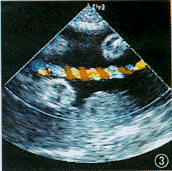

1.脐血流变化:我们观察到脐带血流有几种形态变化,基本上分为3类型。(1)“川”字形(图1);$形(图2)。多数这两种形态并存,并在同一切面上,脐静脉几乎呈直线状,动脉与静脉显示的长度不一致。(2) 扭麻绳状(图3),这种形态少见,且在1个切面上动脉与静脉长度显示几乎相等排列。既脐静脉不能直线行走,与动脉血流呈间断显示。

图3 脐带血流呈扭麻绳状,动静脉长度一致